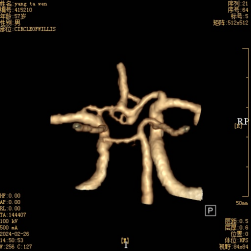

術(shù)前頭顱CTA提示:前交通動(dòng)脈瘤,前交通動(dòng)脈復合體不規則膨大,有多個(gè)囊狀分葉(如箭頭所示)

術(shù)后頭顱CTA提示:前交通動(dòng)脈瘤未顯示(如箭頭所示),雙側大腦前動(dòng)脈A1、A2段及前交通動(dòng)脈動(dòng)脈復合體通暢。